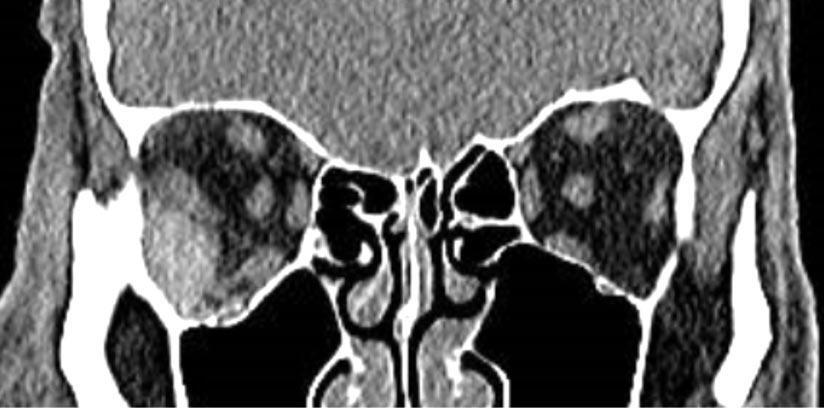

En octubre de 2019, el paciente fue referido a nuestro servicio para evaluación por disminución de la AV; (AV mejor corregida AVMC 6/10 OD y 10/10 OI). En la biomicroscopía (BMC) como se observa en las figuras 1 y 2 de ambos ojos (AO) se constataron precipitados queráti-

cos (PKs) intermedios a gruesos, difusos, células en cámara anterior de 3x y sinequias posteriores (SP). La presión intraocular (PIO) era de 40/20 mm Hg en OD y en OI respectivamente. En el fondo de ojos (figuras 3 y 4) se constató palidez de papila y atrofia peripapilar, retina

Figuras 1 y 2: biomicroscopía de ambos ojos: precipitados queráticos (PKs) intermedios a gruesos, difusos, células en cámara anterior de 3x y sinequias posteriores (SP). Figuras 3 y 4: fondo de ojos derecho e izquierdo: palidez de papila y atrofia peripapilar, retina aplicada y despigmentación difusa (sunset glow fundus).

aplicada y despigmentación difusa (signo de “sunset glow fundus”) por la afectación del epitelio pigmentario de la retina (EPR). Teniendo en cuenta los antecedentes clínicos del paciente, se interpretó el cuadro como un VKHlike, Se inició tratamiento con meprednisona oral 20 mg/kg/día e hipotensores oculares tópicos (timolol + dorzolamida). La respuesta antiinflamatoria fue satisfactoria ya que en los controles subsiguientes no se observaban PKs ni células en cámara anterior, sin embargo, la PIO en OD persistió elevada pese al tratamiento hipotensor. En la gonioscopía (figuras 5 y 6) se constató ángulo cerrado con sinequias en los 360º, por lo que se